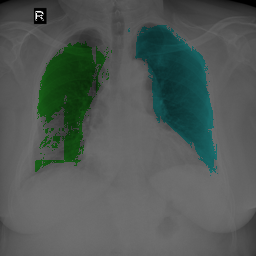

To bridge the methodological gaps when only small-scale partially labeled data is available, we propose a simple yet efficient framework Vicinal Labels Under Uncertainty (VLUU) by exploring the statistical similarity of human structures (e.g. shape, size, location) among different patients. See Fig. 1 for an illustration of such a similarity. The proposed framework is motivated by vicinal risk minimization (VRM) [11], where the fully labeled vicinal examples are generated by linearly combining randomly sampled partial labels with a weight randomly sampled from a Dirichlet distribution. These vicinal examples allow us to transform the partially supervised problem into a fully supervised one. That is to say, we can utilize any existing supervised segmentation networks and loss functions to solve partially supervised problems. The generated vicinal labels contain uncertainty regions where classes of interest could potentially overlap. We utilize these uncertainties in the training process to improve the robustness of DL models.

In standard adversarial training, the segmentation network and the discriminator play a zero-sum game. The discriminator is trained to discriminate the prediction masks produced by the segmentation network from the ground truth masks. Meanwhile, the segmentation network is trained to confuse the discriminator by producing realistic prediction masks. Adversarial training benefits from the human structure similarity as it makes the unknown true label distributions easier to be caught by the discriminator than for general objects [38]. In other words, there is smaller instance-wise variation in the size, shape, and location of human organs (or structures), as shown in Fig. 1, than for general objects.